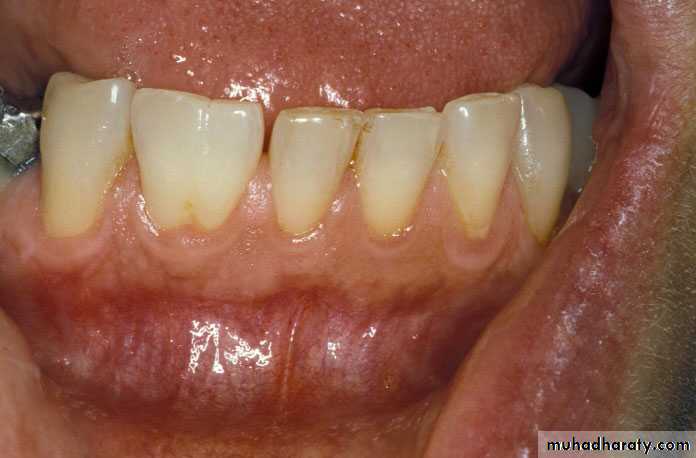

Dentinogenesis imperfecta

It’s a genetic disorder of tooth development, this condition causes teeth to be discolored (most often a blue-grey or yellow-brown color) and translucent. Teeth are also weaker than normal, making them prone to rapid wear, breakage and loss. These problems can affect both primary and permanent teeth.Cause

Inherited defect in collagen formationTreatment

Treatment involves placement of stainless steal crowns on the teeth at least on the posterior region and composite resin on anterior teeth.